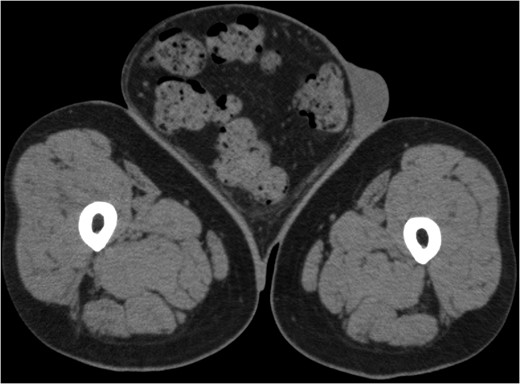

A 73-year-old man was referred to our hospital by his primary care doctor because of a bulge in his right inguinal region. The patient reported this bulge had been present since his adolescence. The hernia had been reducible until age 55, and had become irreducible, thereafter. Medical history included hypertension, diabetes mellitus, asthma and cerebral infarction. He was currently taking one aspirin daily. The patient was 159 cm tall and weighed 84 kg, with a body mass index of 32.2 kg/m2. On physical examination, the bulge in his right inguinal region was roughly the size of an infant's head and the bottom of scrotum descended to his knees in the upright position (Fig. 1). Laboratory tests indicated a hemoglobin A1C (HbA1C) concentration of 7.0% and a urine glucose concentration of 4+. Lung function tests identified restrictive lung function and pre-operative cardiac ultrasound revealed no local asynergy. Abdominal computed tomography (CT) imaging identified the sigmoid colon with a large amount of feces and the great omentum as part of the contents of the hernia (Fig. 2). Although the hernia was irreducible, the patient was planned to undergo an elective surgery for hernia repair due to absence of symptoms of incarceration. Informed consent was obtained from the patient. The patient achieved a weight reduction of 3 kg within 3 months prior to surgery.

Computerized tomography image of the hernia on admission, indicating the sigmoid colon, including a large amount of feces inside the sigmoid colon, and the greater omentum as part of the contents of the hernia.

CT on the day of admission showed a hernia sac of 2263 ml, with an intra-abdominal volume of 12 021 ml. Pre-operative bowel preparation with Magcorol P reduced the volume of the hernia contents to 1604 ml, representing a 71% reduction. The intra-abdominal volume was decreased to 10 485 ml.